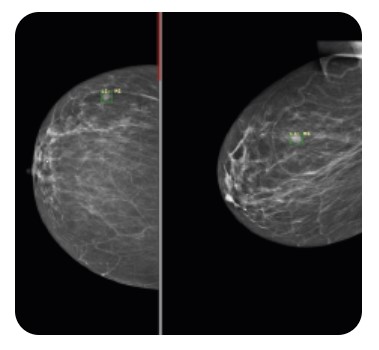

Carebot AI MMG

Carebot AI MMG - Rozwiązanie dla badań mammograficznych

Oprogramowanie stworzone do szczegółowej analizy zdjęć mammograficznych. Obiektywnie ocenia gęstość tkanki piersiowej zgodnie z BI-RADS. Użytkownik otrzymuje alert o występowaniu mikrozwapnień, asymetrii gęstości i zmian patologicznych oraz punktową ocenę ryzyka ich złośliwości. Predykcje AI są wyraźnie prezentowane bezpośrednio na zdjęciu w systemie PACS.